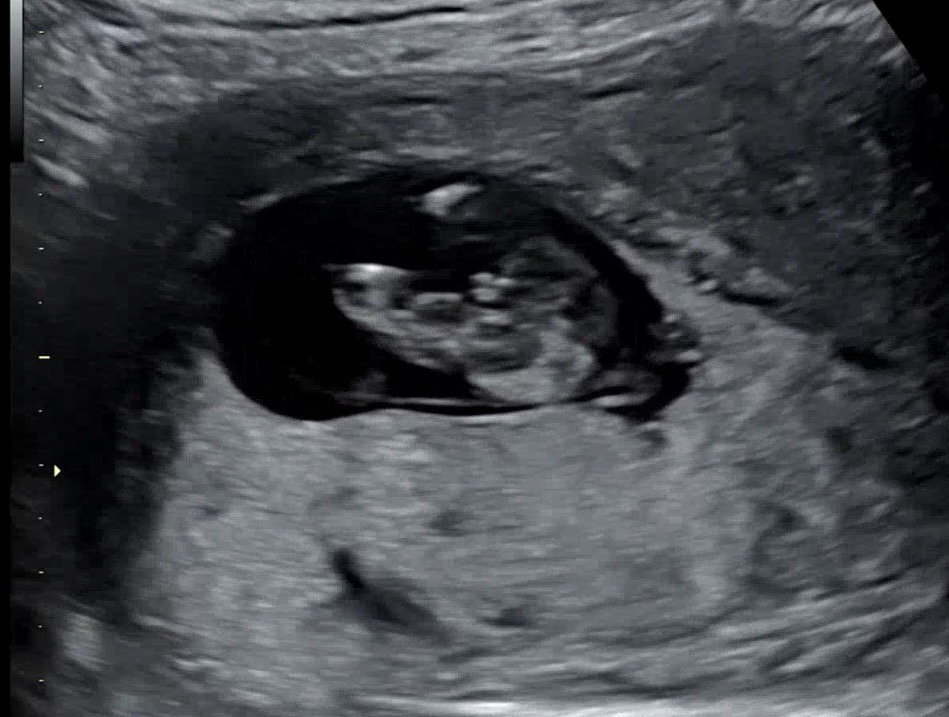

13주 0일 삼각점 고추???

추석껴서 정밀초음파를 12주에 못하고 13주0일에 했는데요~ 이 시기엔 성기가 다 튀어나와있는 기간이라는데 엉덩이 밑에서 찍은게 존재감이 넘 확실해보여서요 ㅋㅋㅋ 첫째도 12주때 고추같은게 보였는데 16주에 확인결과 딸이었거든요? 근데 이번엔 첫째때보다 더 도드라져 보이는거 같아서ㅋㅋ 엉덩이 밑 사진 올립니당 남아일까요? 아님 달라질수도 있으려나요?ㅋㅋ